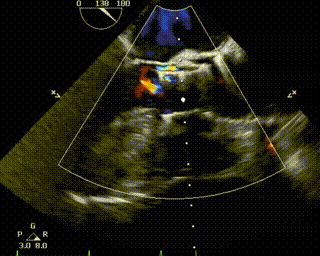

患者为68岁男性,因心悸胸闷入院。术前超声报告显示,患者为功能型二叶式主动脉瓣,右无融合钙化,主动脉瓣明显增厚钙化,瓣叶开放受限,主动脉瓣前向血流加速Vmax=4.2m/s,平均跨瓣压差36mmHg,有效开口面积0.7cm²,舒张期瓣口中度反流信号。

术前、术后超声对比